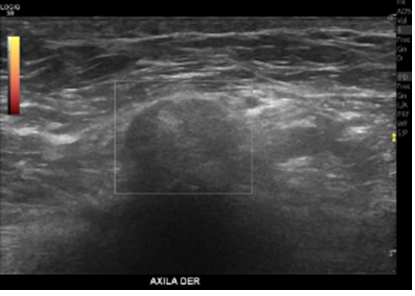

Se realiza posteriormente Ecografía Mamaria

Descripción de hallazgos:

Hallazgos TM:

En la axila derecha adyacente a cabeza de húmero y en correlación con reg. palpable, se observa área nodular hipoecogénica, ovalada y parcialmente circunscrita, sin señal al Doppler Power, podría corresponder a ganglio axilar inespecífico, se sugiere estudio complementario por antecedente de osteosarcoma escapular operado.

En la región axilar derecha se demuestra una imagen nodular isoecogénica de 16x15mm adyacente a la cabeza humeral como hallazgo.

Conclusión:

Nódulo sólido en la mama izquierda bien delimitado.

Como hallazgo incidental imagen nodular de partes blandas adyacente a la cabeza humeral derecha.

Se sugiere estudio con otra técnica diagnóstica ya sea Tomografía computada o RM.